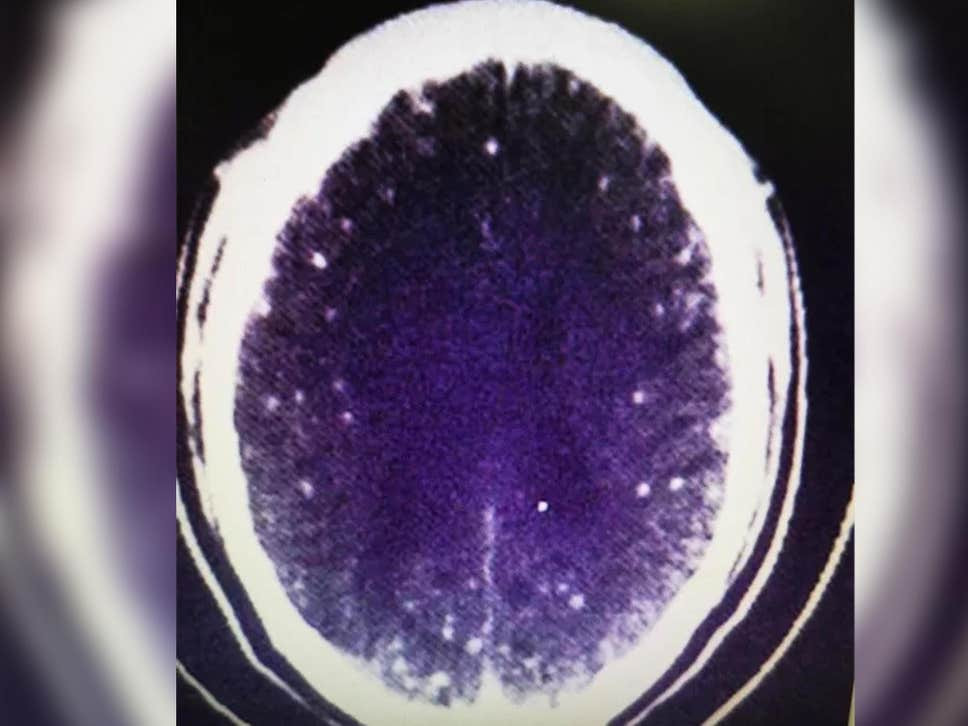

Sau khi thăm khám và chụp cộng hưởng từ cho bệnh nhân, các bác sỹ tại bệnh viện Chiết Giang phát hiện nhiều tổn thương ở 2 bên não cũng như lượng canxi tích tụ bất thường trong mạch máu.

Ảnh chụp cắt lớp não của Zhu. (Ảnh: Bệnh viện Chiết Giang)